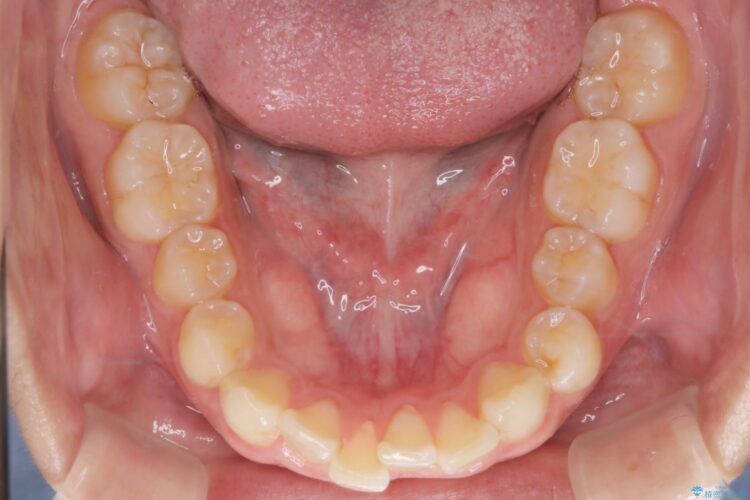

前歯の叢生と口元を下げたいとのことでご来院されました。

その上で今回は抜歯を行わず、歯の表面をわずかに整えるIPRを活用しながら、インビザラインで前歯のガタつきを優先的に改善していく計画を立案しました。

インビザライン矯正により、前歯のガタつきが改善されました。